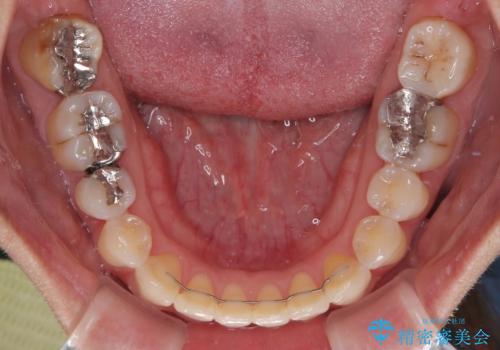

- 1年6ヶ月

- 10-30回

舌の突出癖により、治療過程でスペースが多くできましたが、舌のトレーニングを頑張っていただき、1年強で終えることができました。